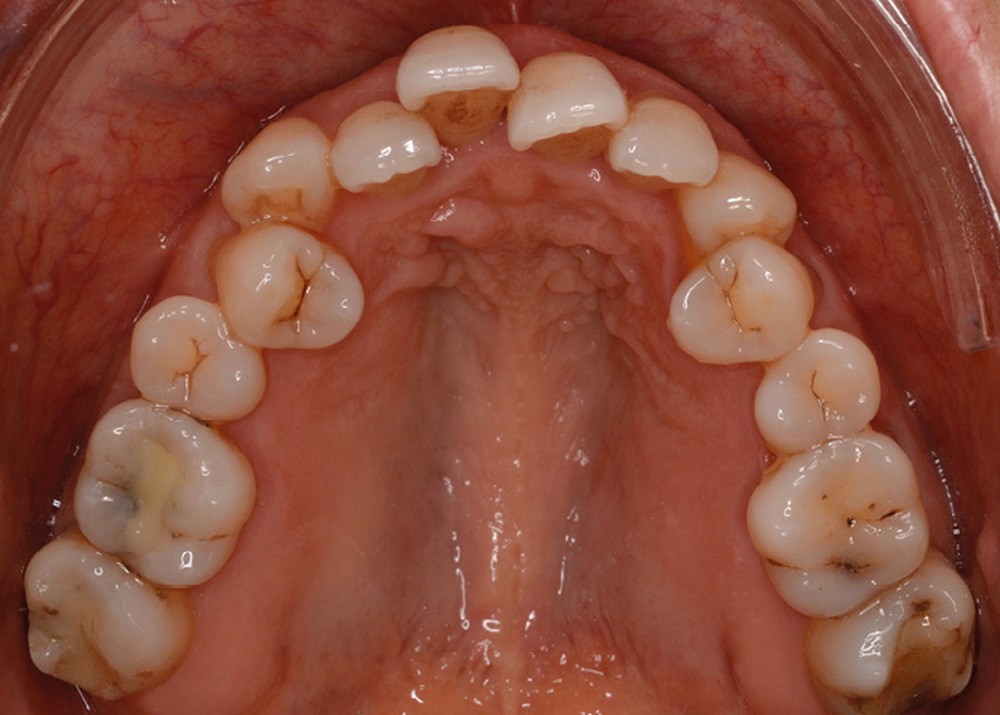

Sur le plan dentaire, la patiente est en classe III droite et gauche, canine et molaire de 6 mm, avec une occlusion inversée antérieure localisée à 11, 12 et 22. Elle présente une dysharmonie dents-arcades sévère, une agénésie d’une incisive mandibulaire est à signaler, et les troisièmes molaires ont été extraites à l’âge de 21 ans.

Au niveau fonctionnel, on note un bruxisme statique avec contact permanent entre les dents maxillaires et mandibulaires. La patiente présente des prématurités en relation centrée sur les incisives, le guidage en propulsion est perturbé et des interférences multiples sont retrouvées en latéralités droite et gauche.